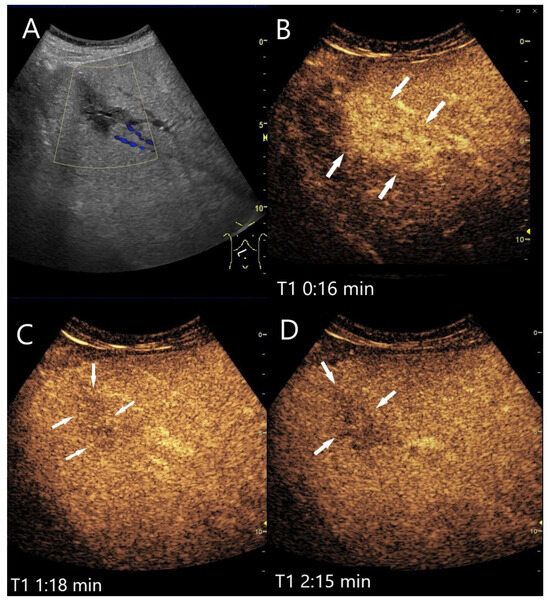

Sarcoidosis. Female patient with multiple hypoechoic liver lesions up to 10 mm. The CEUS shows after 25 s (A), 1 min (B), 2 min (C), and after 3 min (D) a progressive hypoenhancement. The US-guided biopsy revealed a diagnosis of hepatic sarcoidosis.

Figure 15.

Necrotizing sarcoid granulomatosis (NSG) (special form of sarcoidosis characterized by granulomatous vasculitis of the pulmonary veins and pulmonary arteries). Female patient. Multiple confluent hypoechoic focal FLLs (A). CEUS shows progressive hypoenhancement after 1 min (B), 2 min (C), and after 4 min (D). The US-guided biopsy revealed a diagnosis of liver involvement in NSG.